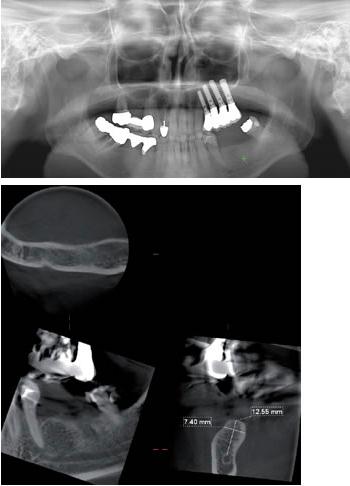

【根尖病巣】

【歯周病】

【インプラント】

CTスキャンは、従来のレントゲンのような平面画像(2次元)ではなく、立体画像(3次元)による高精細な断層写真を撮ることが可能です。

例えば複雑な形態をしている“根”や“骨”などもコンピューターを駆使したデータ処理と画像構成により、正確な診査・診断ができるようになりました。

CTスキャンで撮影した画像は、瞬時に各ユニットのPCにデータが搬送され、即座にビュアー・ソフトを使い360°どの角度からも状態を見ることができます。

CTスキャンの立体画像は、主にインプラントを含む口腔外科分野に威力を発揮しますが、断層方式パノラマX線写真や口内法X線撮影法では判別できない、痛みや症状の原因の究明にも役立っています。